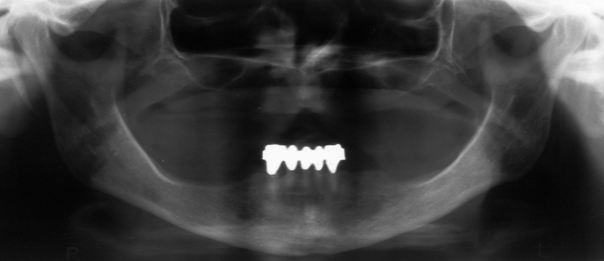

A 74-year-old edentulous woman with osteoporosis and fibromyalgia complained about growing pressure pain of the mandible following extraction of the lower anterior teeth and insertion of mucosa supported complete denture 6 months ago. Her medical history revealed 6 time administration of denosumab (Prolia® 60 mg) subcutaneously over the past 2.5 years. Fibromyalgia was treated with decortin. While intraorally no dehiscence was detected (Figure 1 [Fig. 1]), a panoramic view indicated irregular bone morphology especially in anterior mandible (Figure 2 [Fig. 2]) compared to preoperative imaging 10 months ago (Figure 3 [Fig. 3]). A CT scan illustrated the whole extent (Figure 4 [Fig. 4]). A RANK-Ligand inhibitor (denosumab) associated osteonecrosis of the mandible was diagnosed and reminded us of known BP effects on the jaw. Due to missing dehiscence she was treated conservatively with sultamicillin and prosthesis leave for 2 months with slight improvement of complaints. On the other hand with respect to the great extent of the osteonecrosis, we clarified the potential need of microvascular free flap for reconstruction.

Figure 2: Panoramic view reveals edentulous site after extraction and disturbed presentation of mainly anterior part of the mandible